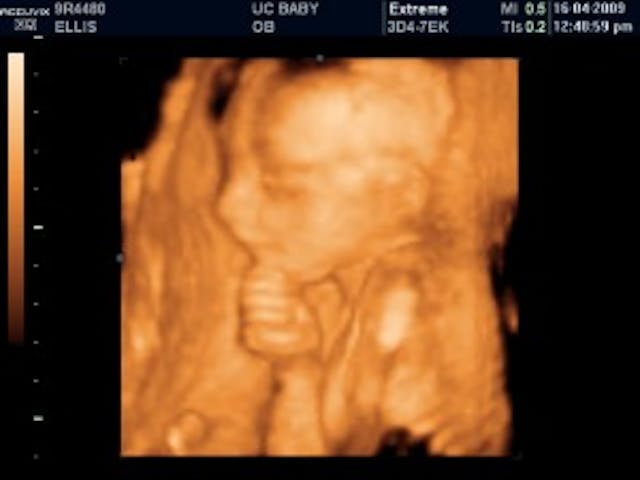

4) The Ponderer

This little baby’s pics got posted on the website BabyGaga in a contest for the best ultrasound pic. This preborn cutie reminds me of the bronze statue, ‘The Thinker’. Since this baby’s holding his chin instead of resting his head on it, I’ll assume he’s in deep thought and call him/her ‘the ponderer’. Perhaps he’s wondering when he’ll make his entrance into the earth.